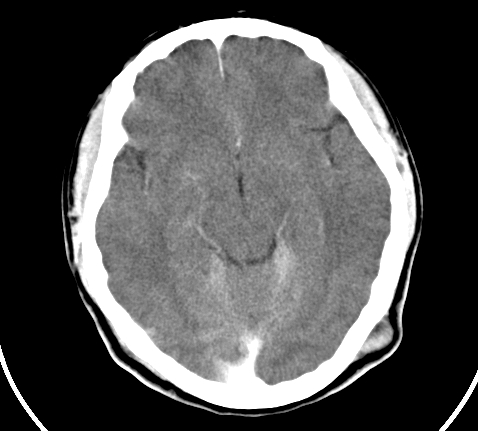

标题: CT23915:女 20岁 全身长疙瘩三年 今日多体位查 看看吧 [打印本页]

标题: CT23915:女 20岁 全身长疙瘩三年 今日多体位查 看看吧

神经纤维瘤病

支持神经纤维瘤。

支持 神经纤维瘤病。